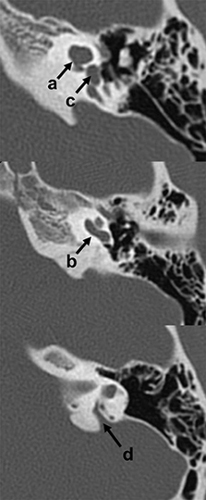

Cortes axiales de tomografía computada (TC) del hueso temporal izquierdo. Paciente con hipoacusia neurosensorial bilateral congénita. Se observó fusión de los giros apical y medio de la cóclea (a) con conservación del giro basal (b). Nótese también la presencia de dilatación del vestíbulo (c) y acueducto vestibular (d).